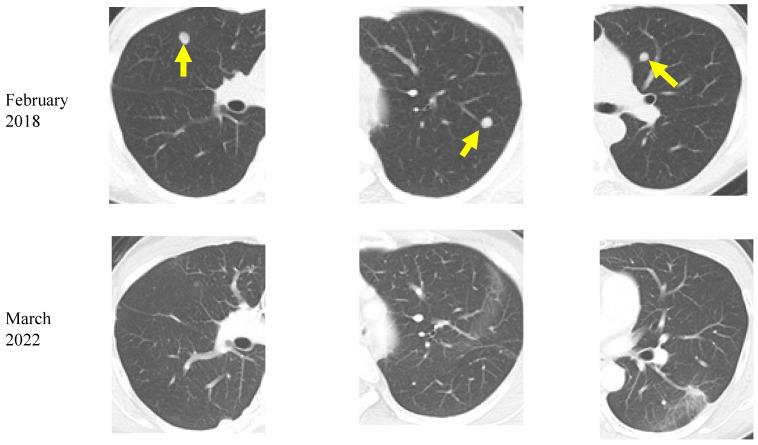

A ketogenic diet has been proposed as a potential supportive therapy for cancer patients, although its long-term influence on survival rates remain controversial. In our previous report, we presented promising results for 37 of 55 patients with advanced cancer enrolled between 2013 and 2018 who remained on a ketogenic diet for at least 3 months. We followed all 55 patients until March 2023 and analyzed the data up to March 2022. For the 37 patients with previously reported promising results, the median follow-up period was 25 (range of 3-104) months and 28 patients died. The median overall survival (OS) in this subset of 37 patients was 25.1 months and the 5-year survival rate was 23.9%. We also evaluated the association between the duration of the ketogenic diet and outcome in all 55 patients, except for 2 patients with insufficient data. The patients were divided into two groups: those who followed the diet for ≥12 months ( = 21) and those who followed it for <12 months ( = 32). The median duration of the ketogenic diet was 37 (range of 12-99) months for the ≥12 months group and 3 (range of 0-11) months for the <12 months group. During the follow-up period, 41 patients died (10/21 in the ≥12 months group and 31/32 in the <12 months group). The median OS was 19.9 months (55.1 months in the ≥12 months group and 12 months in the <12 months group). Following the inverse probability of treatment weighting to align the background factors of the two groups and make them comparable, the adjusted log-rank test showed a significantly better OS rate in the group that continued the ketogenic diet for a longer period ( < 0.001, adjusted log-rank test). These results indicate that a longer continuation of the ketogenic diet improved the prognosis of advanced cancer patients.